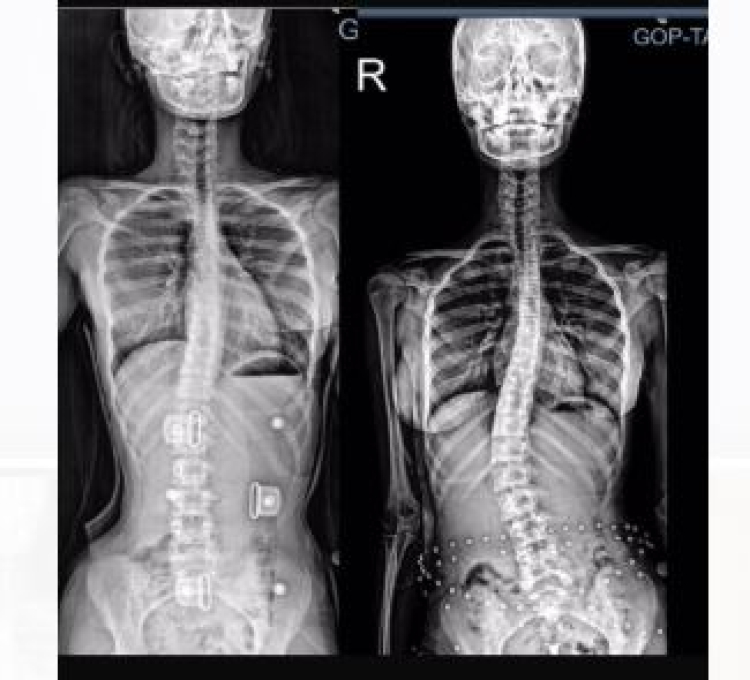

Skolyoz, omurganın yana doğru eğilmesiyle oluşan bir iskelet sistemi bozukluğudur. Çoğunlukla çocukluk veya ergenlik döneminde ortaya çıkar. Eğriliğin ilerlemesini durdurmak ve omurgayı desteklemek için erken müdahale büyük önem taşır.